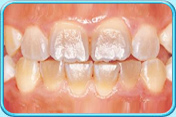

有橙色漬的牙齒牙齒沒給清潔乾淨,積聚在表面的牙菌膜含有一些能發出顏色的細菌或真菌,形成綠色或橙色的漬。

牙科醫生會藉洗牙以清除積聚的牙菌膜及色素。

清除橙色漬後的牙齒每天早晚刷牙和使用牙線徹底清除牙菌膜,以保持牙齒潔白。